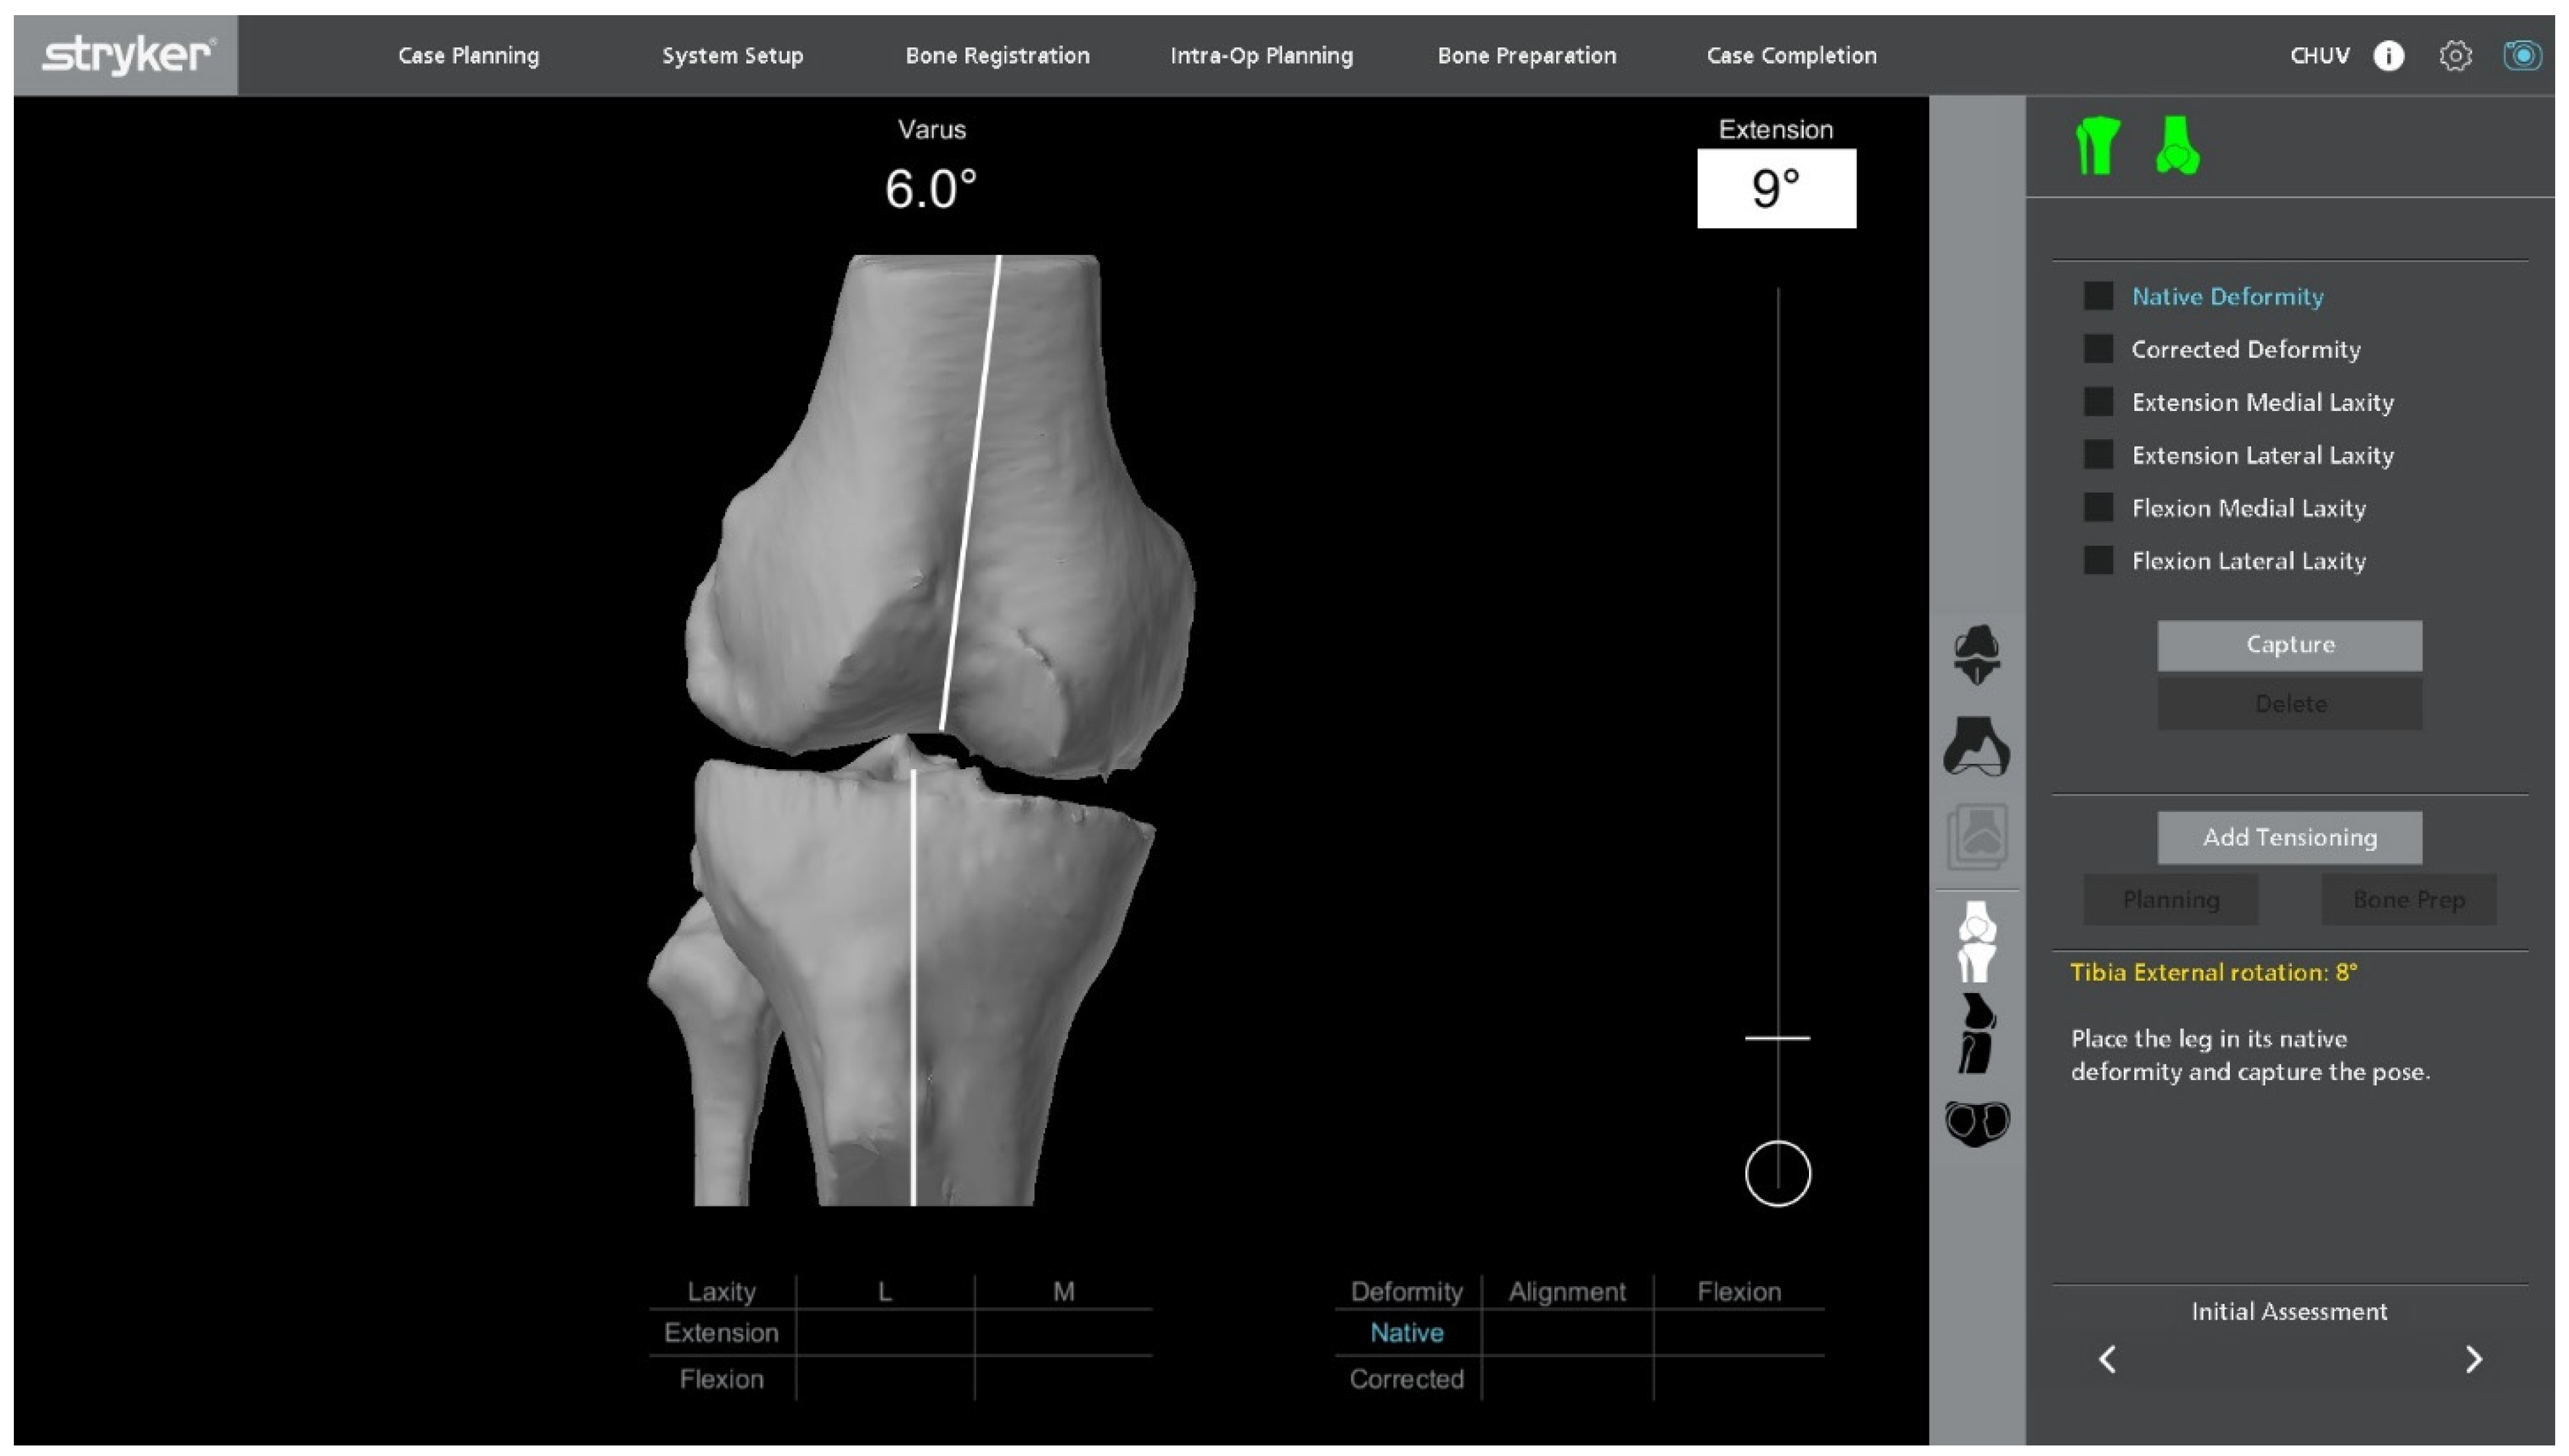

2.4. Intraoperative Functional Alignment and Ligament Balance Assessment

With the UKA components in place, an initial intraoperative functional alignment assessment is performed (Figure 3). The polyethylene insert is reinserted to enable a dynamic evaluation of ligament balance in both flexion and extension, providing essential data for potential plan adjustments. After registration and verification of reference points, this assessment is repeated through the full range of motion, allowing real-time adaptation to refine the 3D plan.

Figure 3.

Intraoperative ligament balance assessment after registration. The polyethylene insert is reinserted prior to implant removal to evaluate dynamic ligament balancing through flexion and extension.

Varus–valgus stress tests are applied at multiple flexion angles to assess ligament balance. The target is 1–2 mm of controlled laxity with symmetric medial and lateral gaps in extension and at 90° of flexion. The medial–lateral side-to-side difference should be ≤1 mm to maintain optimal soft-tissue tension and avoid mid-flexion instability.